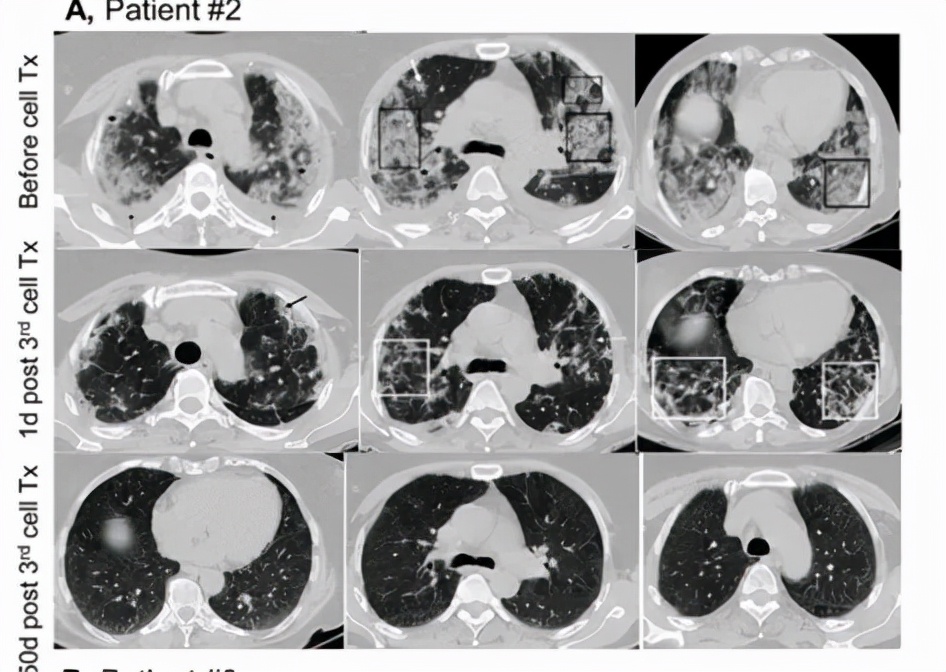

03影像学评估显著改善

输注间充质干细胞前进行了肺部CT扫描,所有病例均有明显的肺部受累,3例存活患者经治疗后行肺部CT检查,其中两名患者的肺部CT扫描显示, 在完成间充质干细胞治疗后,肺部阴影明显消退,胸膜下病灶完全消退。

图片来自文献[1]